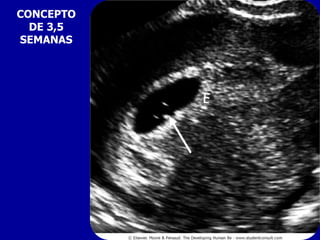

CONCEPTO

DE 3,5

SEMANAS

CONCEPTO DE3,5 SEMANAS